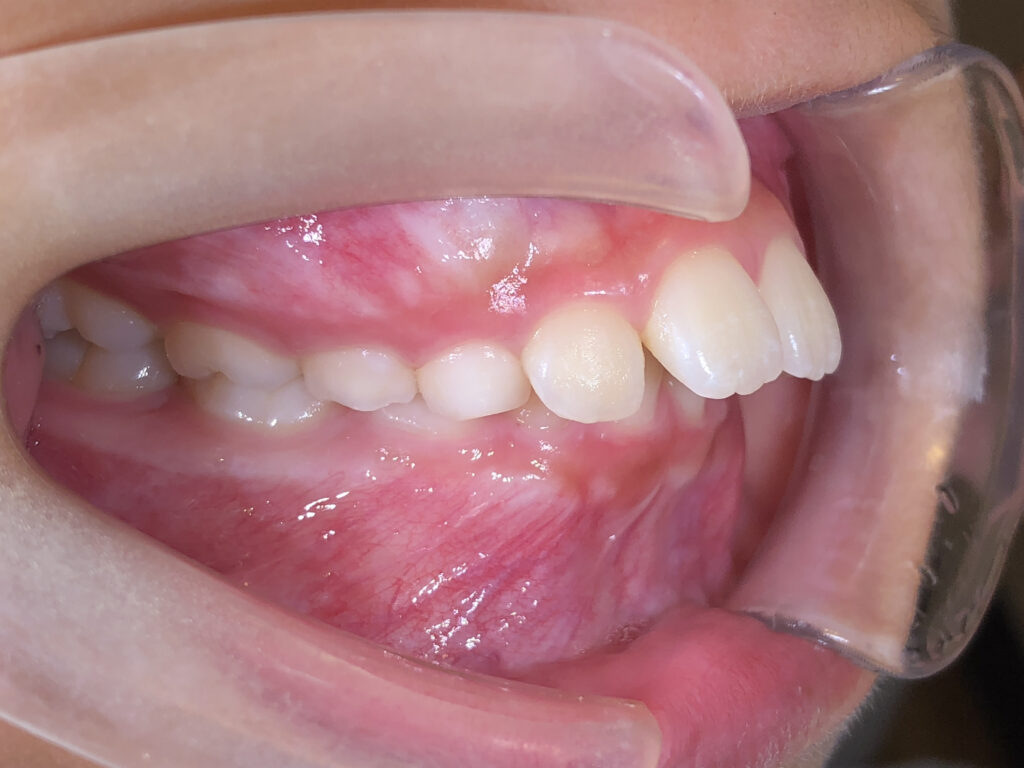

右側

治療後